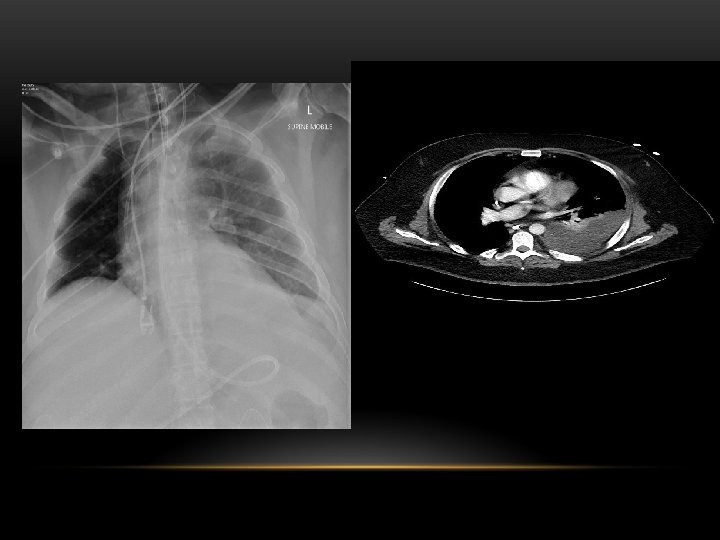

Pneumothorax • No vascular markings on right • No shift of mediastinum to left • Atelectasis right lung • Increased haziness on left: Diversion of entire cardiac output • Small fluid level near costophrenic angle: Hydro pneumothorax

Tension Pneumothorax • No vascular markings on right • Shift of mediastinum to left • Atelectasis right lung • Increased haziness on left: Diversion of entire cardiac output

Tension pneumothorax : is the progressive build-up of air within the pleural space, usually due to a lung laceration which allows air to escape into the pleural space but not to return. Positive pressure ventilation may exacerbate this 'one-way-valve' effect. Progressive build-up of pressure in the pleural space pushes the mediastinum to the opposite hemithorax, and obstructs venous return to the heart. This leads to circulatory instability and may result in traumatic arrest.